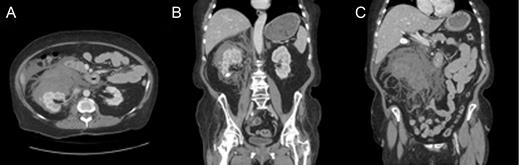

A pre- and post-contrast CT scan of the abdomen and pelvis revealed a large right perinephric hematoma within the anterior aspect of the retroperitoneum (Fig. 1). This hematoma distended the renal fascia, crossed the midline and displaced other peritoneal and retroperitoneal structures. Free fluid and a hyperdense focus of vascular contrast were present adjacent to the hematoma. The estimated size of the hematoma was 13 cm in the cephalocaudad, 12 cm in the transverse and 8.5 cm in the anteroposterior dimension. The vena cava, renal artery and renal vein were narrowed likely due to vasospasm, but the aorta was otherwise unremarkable.

Peri- and paranephric hematoma filling the right retroperitoneum. Pre-contrast and contrast enhanced abdominal and pelvic CT with (A) axial, and (B and C) coronal views. The hematoma distends the renal fascia, crosses the midline and displaces other peritoneal and retroperitoneal structures. Free fluid, and a hyperdense focus of vascular contrast is present adjacent to the hematoma (best seen in A). An incidental ∼18 mm right lower pole renal calcification (B). The estimated size of the hematoma was 13 × 12 × 8.5 cm. Incidental finding of cholelithiasis (C)